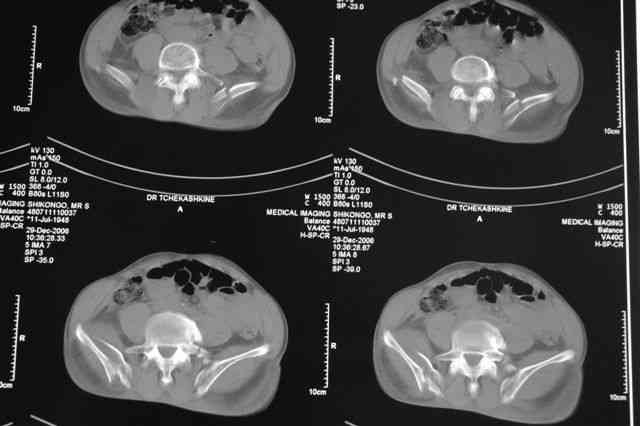

В приложении отправляю послеопер. снимки бедра и лодыжки обсуждаемого вчера больного.

В приложении послеоперационные картинки.

Чекашкин Е.И.